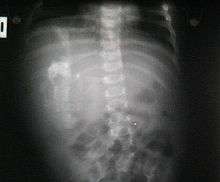

Fetus in fetu (or foetus in foetu) is a developmental abnormality in which a mass of tissue resembling a fetus forms inside the body. There are two theories of origin concerning "fetus in fetu". One theory is that the mass begins as a normal fetus but becomes enveloped inside its twin.[1] The other theory is that the mass is a highly developed teratoma. "Fetus in fetu" is estimated to occur in 1 in 500,000 live births.[2]

A fetus in fetu can be considered alive, but only in the sense that its component tissues have not yet died or been eliminated. Thus, the life of a fetus in fetu is akin to that of a tumor in that its cells remain viable by way of normal metabolic activity. However, without the gestational conditions in utero with the amnion and placenta, a fetus in fetu can develop into, at best, an especially well differentiated teratoma; or, at worst, a high-grade metastatic teratocarcinoma. In terms of physical maturation, its organs have a working blood supply from the host, but all cases of fetus in fetu present critical defects, such as no functional brain, heart, lungs, gastrointestinal tract, or urinary tract. Accordingly, while a fetus in fetu can share select morphological features with a normal fetus, it has no prospect of any life outside of the host twin. Moreover, it poses clear threats to the life of the host twin on whom its own life depends.[3]

Fetus in fetu may be a parasitic twin fetus growing within its host twin. Very early in a monozygotic twin pregnancy, in which both fetuses share a common placenta, one fetus wraps around and envelops the other. The enveloped twin becomes a parasite, in that their survival depends on the survival of their host twin, by drawing on the host twin's blood supply. The parasitic twin is anencephalic (without a brain) and lacks some internal organs, and as such is unable to survive on its own. As the host twin has to "feed" the enveloped twin from the nutrients received over a single umbilical cord, they usually die before birth.